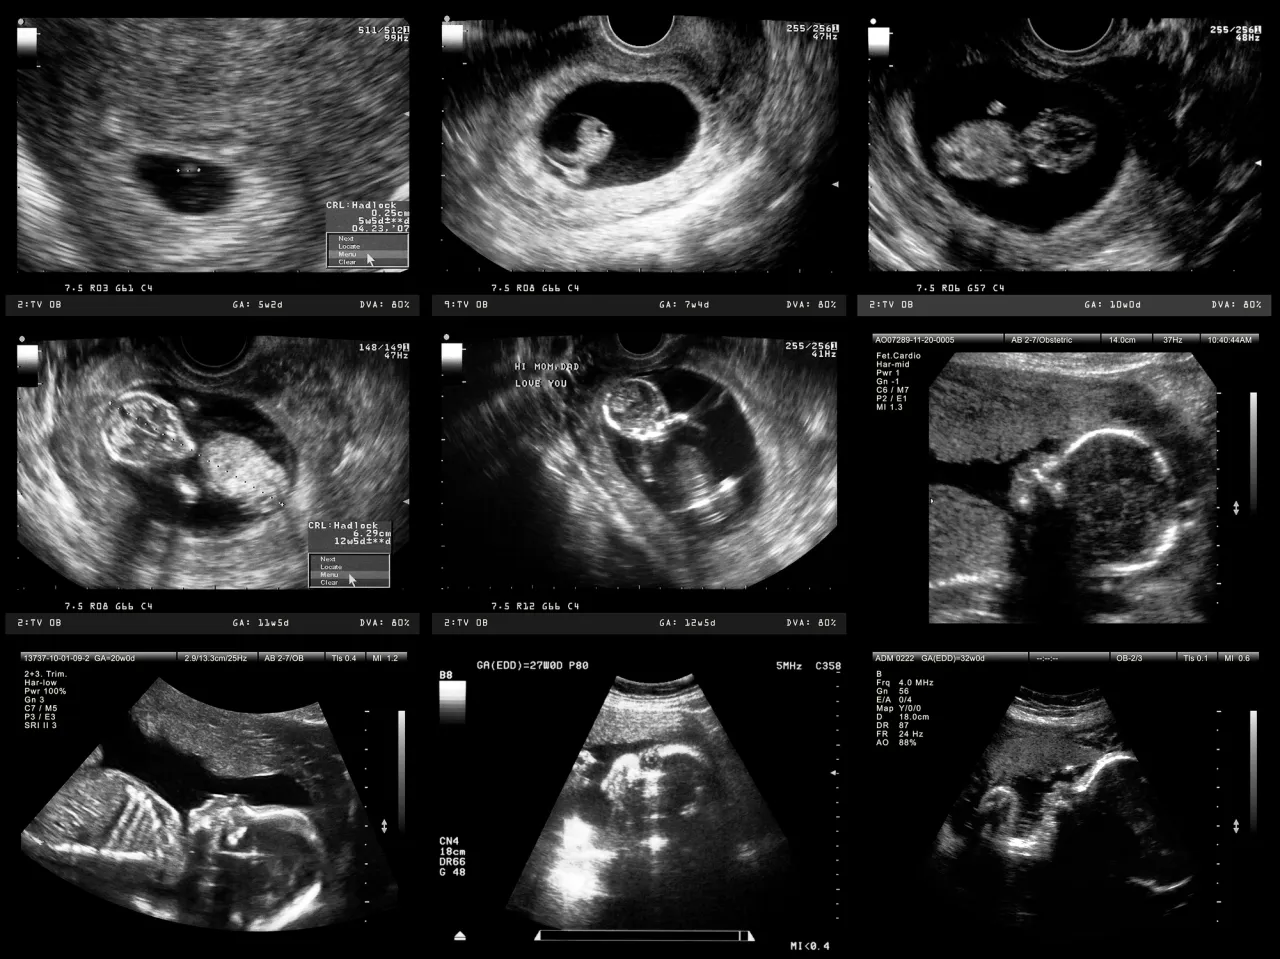

Badanie połówkowe, znane również jako USG II trymestru, to jedno z najważniejszych badań ultrasonograficznych w przebiegu ciąży. Jest ono kluczowe dla dokładnej oceny rozwoju Twojego dziecka i pozwala na wczesne wykrycie ewentualnych nieprawidłowości, co daje spokój i poczucie bezpieczeństwa przyszłym rodzicom.

Badanie połówkowe, określane także jako USG II trymestru lub USG referencyjne, to zaawansowane badanie ultrasonograficzne, które stanowi integralną część opieki prenatalnej. Jest ono uznawane za jedno z obowiązkowych i niezwykle ważnych badań w ciąży zgodnie z wytycznymi Polskiego Towarzystwa Ginekologów i Położników. Jego głównym celem jest przeprowadzenie bardzo dokładnej oceny anatomii płodu, co pozwala na wykrycie lub wykluczenie nawet 90% wad rozwojowych jeszcze przed narodzinami dziecka. To właśnie ta wysoka skuteczność diagnostyczna sprawia, że jest ono tak istotne dla przyszłych rodziców, dając im pewność co do zdrowia maluszka.

Idealnym okresem na wykonanie badania połówkowego jest przedział między 18. a 22. tygodniem ciąży. Ten konkretny czas jest kluczowy, ponieważ dziecko jest już na tyle rozwinięte, że jego struktury anatomiczne są dobrze widoczne i możliwe do szczegółowej oceny. Wcześniejsze badania mogą nie pozwolić na dokładne uwidocznienie wszystkich elementów, podczas gdy późniejsze mogą być utrudnione przez zbyt duże rozmiary płodu i mniejszą ilość miejsca w jamie macicy.

Chociaż badanie można wykonać między 18. a 22. tygodniem ciąży, wielu specjalistów uważa okres między 20. a 22. tygodniem za "złoty standard" w diagnostyce. W tym czasie płód osiąga optymalne rozmiary, co pozwala na uzyskanie najlepszej jakości obrazu ultrasonograficznego. Wszystkie kluczowe narządy i struktury są już w pełni ukształtowane i dobrze widoczne, co minimalizuje ryzyko przeoczenia jakichkolwiek nieprawidłowości rozwojowych. To właśnie dlatego ten przedział czasowy jest często rekomendowany jako najlepszy do przeprowadzenia tego szczegółowego badania.